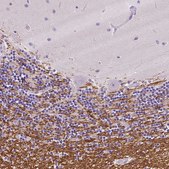

ChIP, IF, IHC

ChIP: 1—10 μg (per reaction), immunofluorescence: 0.25-2 μg/mL, immunohistochemistry: 1:500-1:1000

All Prestige Antibodies Powered by Atlas Antibodies are developed and validated by the Human Protein Atlas (HPA) project and as a result, are supported by the most extensive characterization in the industry.

The Human Protein Atlas project can be subdivided into three efforts: Human Tissue Atlas, Cancer Atlas, and Human Cell Atlas. The antibodies that have been generated in support of the Tissue and Cancer Atlas projects have been tested by immunohistochemistry against hundreds of normal and disease tissues and through the recent efforts of the Human Cell Atlas project, many have been characterized by immunofluorescence to map the human proteome not only at the tissue level but now at the subcellular level. These images and the collection of this vast data set can be viewed on the Human Protein Atlas (HPA) site by clicking on the Image Gallery link. We also provide Prestige Antibodies® protocols and other useful information.

• IHC tissue array of 44 normal human tissues and 20 of the most common cancer type tissues.